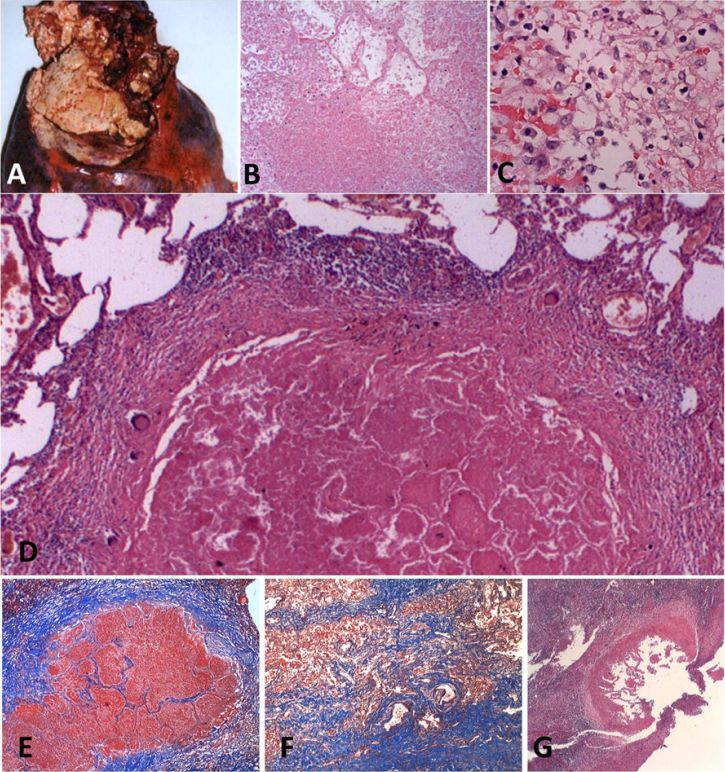

虽然干酪样肉芽肿在原发性结核病后的形成阶段不存在,但它们确实在慢性疾病期间出现,似乎是愈合过程的一部分,并与广泛的纤维化有关。小面积的陈旧性非活动性结核性肺炎通常被肉芽肿包围,周围有上皮样细胞、巨细胞和淋巴细胞,见图7D。这种病变愈合后可能只留下纤维性疤痕。在大面积干酪样肺炎的病例中,结节的形成始于干酪样的周围,外观相似,但进展为纤维样结核,图7E-F。常见的是发现多个纤维组织的同心圆,表明病变进展,然后在不同时机愈合。这种干酪样肉芽肿作为原发性肺结核后慢性或治愈过程的一部分发展的模式,在1882年Ewart的《古斯顿人》的讲座中和后来的作者都清楚地描述过。干酪样肉芽肿偶尔可见空洞,但与干酪样肺炎的碎片相比,它们最多是次要的组成部分,图7G。

图7.慢性纤维干酪性结核病。大量干酪样肺炎不能软化和碎片化而产生空洞,可能只是停留在相对不活跃的状态。在本例中,肺上叶坏死伴干酪样肺炎,已干尸化(A)。显微镜下,它由干酪样肺炎构成,邻近富含脂质结核性肺炎(B,C)的生存区(H & E染色100-400倍放大)。老年干酪样肺炎常被肉芽肿组织包围(D)。中央坏死核心保留干酪样肺炎的肺泡结构,周围是活跃的肉芽肿,有上皮样细胞、巨细胞和淋巴细胞,但没有泡沫状巨噬细胞。纤维化围绕着干酪样肺炎的小区域(E),或扩展到肺的大区域并伴有较大的病变,从而产生肺纤维化(F)。多层纤维化显示病变在不同的情况下进展和消退(G)。(三色染色40倍放大)。很少见到干酪样肉芽肿侵蚀入空洞(G)。然而,病变往往很小,很难清楚空洞是否侵蚀成肉芽肿或反之亦然。